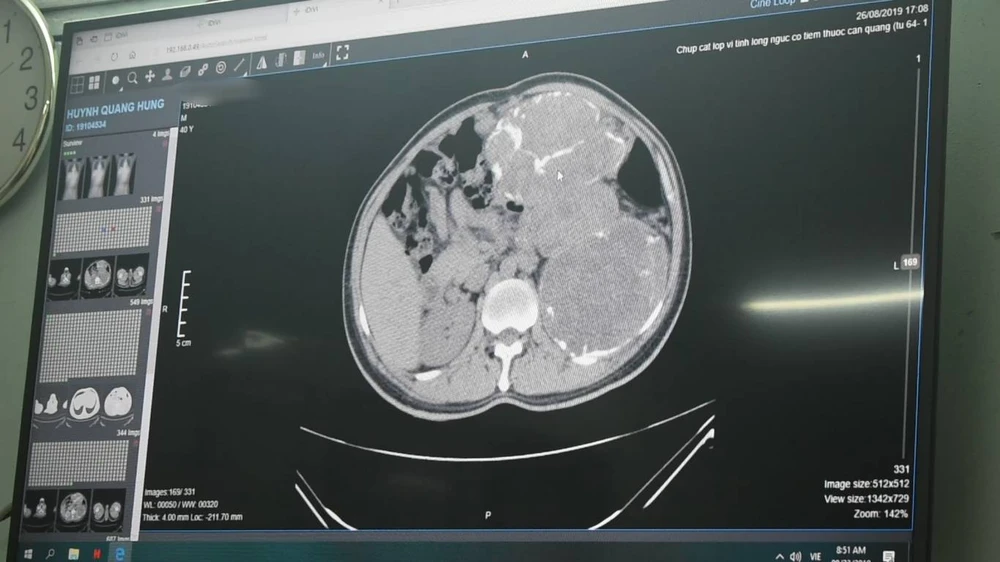

Bệnh nhân nhập viện với tình trạng bụng chướng to và được cho chụp CT cắt lớp có cản quang, phát hiện ba khối u choán chỗ nằm sau phúc mạc ở phần ổ bụng bên trái, mỗi khối đường kính khoảng 14,5 cm. Ba khối u khá lớn đã xâm lấn và đẩy lách, thận trái nằm lệch chỗ, các tĩnh mạch dẫn lưu đổ vào tĩnh mạch mạc treo giãn lớn.

Ba khối u choán ổ bụng của bệnh nhân. Ảnh: ĐL